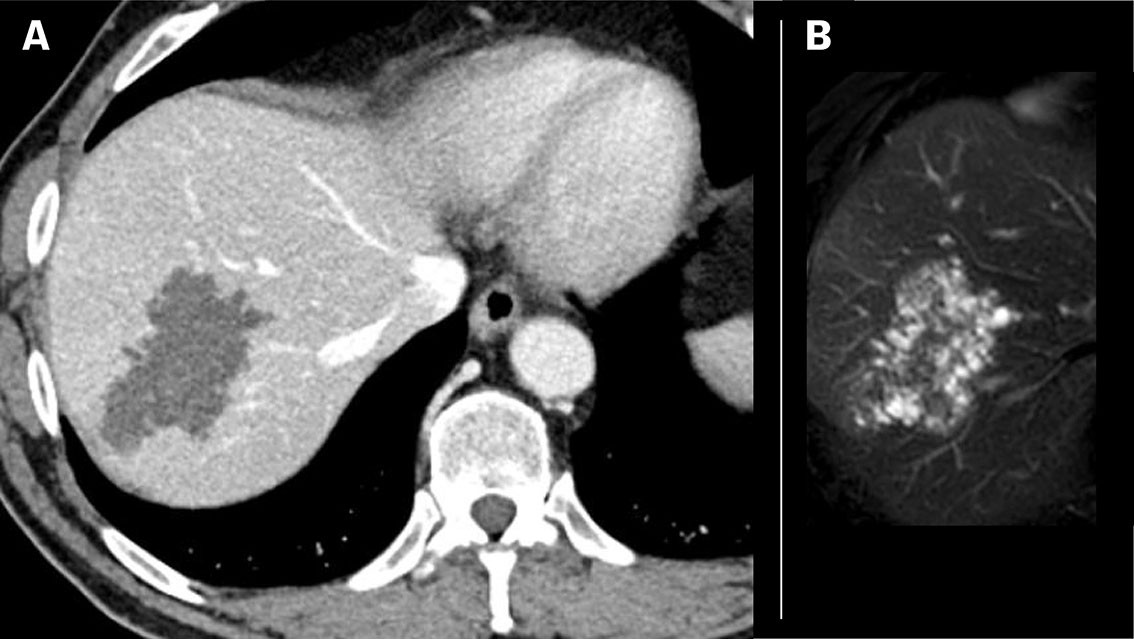

Patient 2: A man in his sixties from Eastern Europe, who has lived in Norway for many years, was examined for newly diagnosed colorectal cancer. CT abdomen revealed a 3 cm large lobular lesion in liver segment 7. The lesion was perceived to be a hemangioma. At a CT check-up one year later, the lesion had grown to 6.5 cm, and metastasis was initially suspected, but MRI of the liver surprisingly revealed multiple small cysts (Figure 3). Serological testing detected antibodies to E. multilocularis . The patient started on albendazole and a right hemihepatectomy was performed. The surgical specimen contained a large multicystic tumour (Figure 4). Histological findings were typical for alveolar echinococcosis (Figure 5). The patient developed moderately elevated liver transaminases, and albendazole was temporarily discontinued. After several attempts at reintroduction, albendazole was finally discontinued seven months after the operation. Six-monthly check-ups are planned for several years with radiology and serology to monitor for potential relapse.

Diagnosis of alveolar echinococcosis is based on a combination of typical radiological findings positive serology. The final diagnosis is made after histopathological examination and/or PCR analyses of the surgical specimen. Alveolar echinococcosis is classified radiologically according to CT findings (Alveolar Echinococcosis Ulm Classification for Computed Tomography , AEUC-CT ) and MRI (Kodama's classification) (3,4) . The lesions often present on CT as lobulated masses with poorly demarcated margins, irregular central necrosis and scattered calcifications suggestive of a malignant tumour, but the characteristic microcystic components present more clearly on MRI (Figures 1 and 3). MRI is best suited for characterisation and locoregional spread. The diagnosis is generally not based on diagnostic imaging alone, as several other focal hepatic lesions, including premalignant and malignant tumours, can have similar characteristics (5) . An FDG PET scan is useful for initial diagnosis as well as for postoperative monitoring and when relapse is suspected (6) .